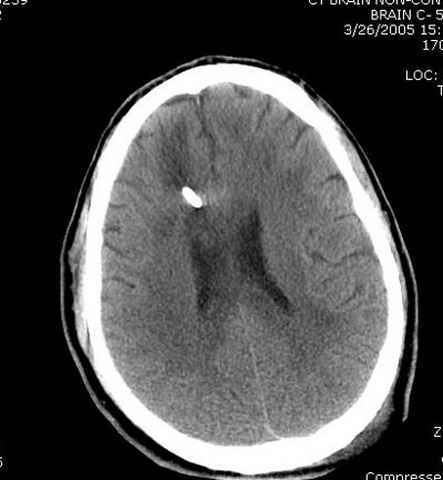

03.14.2005

больному 42, автоавария, политравма, открытая черепномозговая травма, безсознании, открытый перелом бедра, размозжение мягких тканей, дефект кожи на передней поверхности бедра около 13 см2 от ожога, компартмент синдром.

По поводу открытого перелома больной ургентно взят на ретроградное интрамедулярное штифтование, после рутинного дебрайдмента и фасциотомии на бедре и на голени.

Наблюдается службой травмы и нейрохирургии (ICP) Increased Intracranial Pressure by ventricular cateter

постоперационные

монииторинг